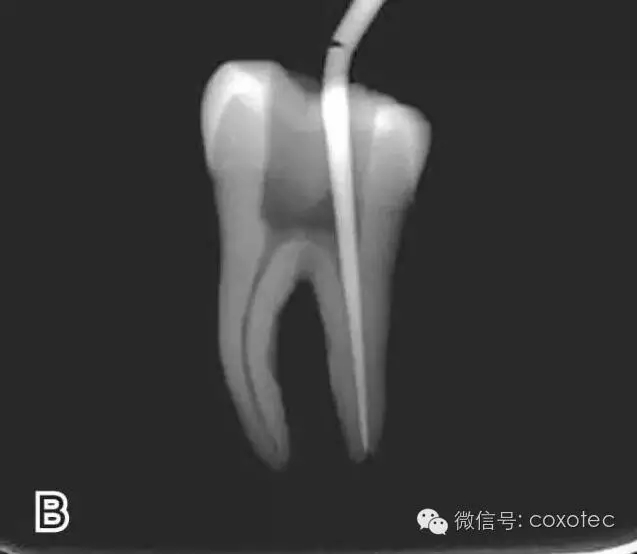

將攜熱器工作尖向根尖加熱加壓至距參照點(diǎn)約2 mm處,關(guān)閉加熱器,保持根向壓力,使工作尖前進(jìn)到參照點(diǎn)處。保持加壓狀態(tài)10秒鐘(圖6)。

圖6 連續(xù)加壓,A、B.?dāng)y熱器加壓